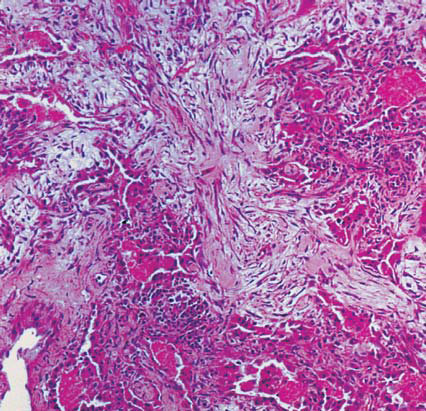

In a patient with ARDS, the lung biopsy below shows alveolar walls that are thickened by fibroblasts and loose connective tissue. What is the phase? What is the time course? What are the typical findings?

Organizing phase; A week after acute insult; Persistent type II pneumocytes and interstitial inflammation with absent hyaline membranes.